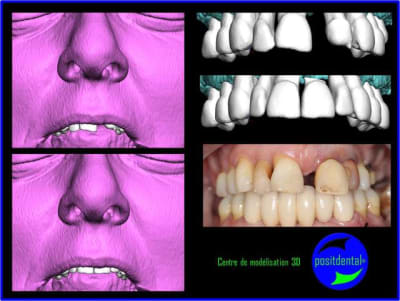

1er étape le wax-Up, dans ce cas clinique il est réalisé en 3D

Cette vidéo présente une gestion de l'esthétique dans un cas d'extraction, implantation, mise en charge immédiate alors qu’il ne reste pas de chicot mais des dents mobiles.